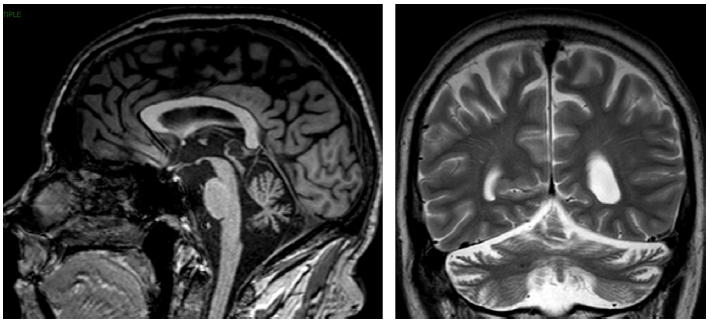

表5总结了四种遗传性共济失调,这四种遗传性共济失调均很常见小脑萎缩。图9显示的是痉挛性共济失调相关的小脑萎缩。图10显示的是线粒体疾病相关的小脑萎缩。运动障碍如震颤和Kayser-Fleischer环的存在应考虑Wilson病(图11)。大多数SCA可见进行性橄榄小脑萎缩(图12和13)。

图10 线粒体疾病相关的小脑萎缩。图为头颅MRI T1加权序列矢状位图像。

图11 Wilson病患者头颅MRI 影像。头颅MRI FLAIR序列显示Wilson病中的顶盖和小脑中脚的高信号(箭头)。

图12 患者头颅MRI 影像。头颅MRI T1加权序列显示脊髓小脑性共济失调2型(SCA2)相关的小脑萎缩。脑桥稍扁平(箭头,左侧)和小脑扁桃体保留(箭头,右侧)。

图13 患者头颅MRI 影像。头颅MRI T1加权序列矢状位图像显示脊髓小脑性共济失调2型相关的小脑和脑干萎缩。脑萎缩和脑桥扁平(箭头);可能的脊髓变细。